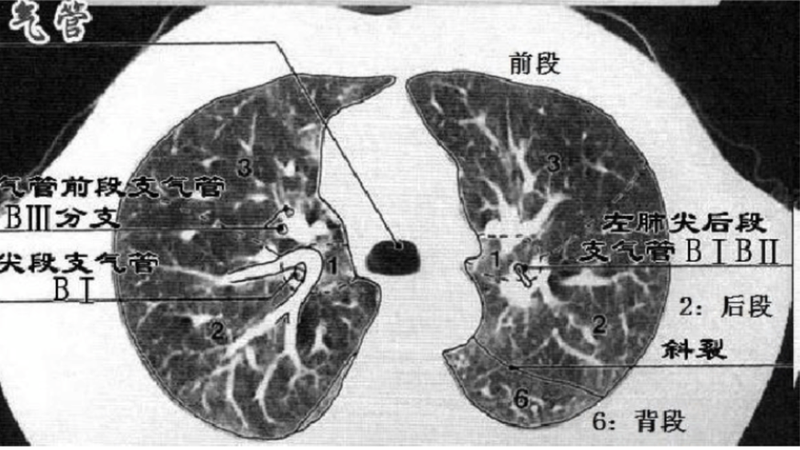

上叶:S1:尖段;S2∶后段;S3:前段。